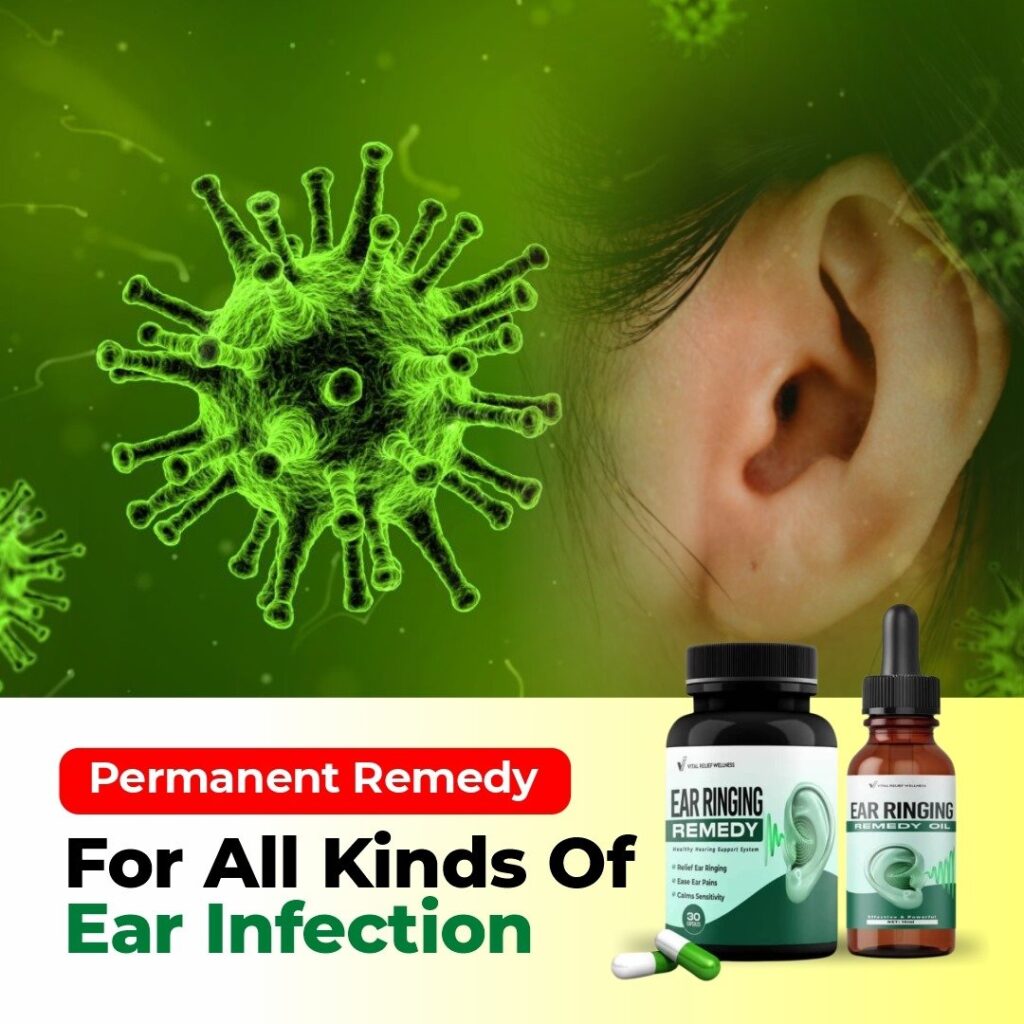

EAR RINGING REMEDY

Reclaim Your Peace From Tinnitus (Ear Ringing) using “Ear Ringing Remedy”

Use Our Ear Ringing Remedy to Revive

- Ear Ringing

- Ear Swelling

- Ear Buzzing

- Ear Pain

INTRODUCING…

Ear Ringing Remedy: Your Path to Quieter Days

“EAR RINGING REMEDY” is a revolutionary, all-natural supplement formulated to address the root causes of tinnitus and offer RELIEF from the constant ringing.

SUPPORTS HEARING HEALTH:The unique blend of vitamins, minerals, and antioxidants in “Ear Ringing Remedy” nourishes hair cells in the inner ear, promoting their health and function.

PROMOTES BLOOD FLOW: Certain ingredients in “Ear Ringing Remedy” improve blood circulation to the inner ear, ensuring proper oxygen and nutrient delivery..

REDUCES INFLAMMANTION: Some components possess anti-inflammatory properties, helping to reduce inflammation in the inner ear that can contribute to EAR SWELLING or tinnitus (EAR RINGING).

SUPPORTS NERVOUS SYSTEM FUNCTION: Specific vitamins and minerals in “Ear Ringing Remedy” support healthy nervous system function, which plays a crucial role in how we perceive sound.

The Benefits of Ear Ringing Remedy:

- Reduced Ringing and Buzzing

- Improved Sleep Quality

- Enhanced Concentration

- Reduced Stress and Anxiety

- Improved Overall Well-being

How To Use…

“Ear Ringing Remedy” offers a convenient and natural approach to address Ear Swelling, Ear Buzzing and tinnitus (Ear Ringing) and find relief from the constant ringing. Here’s how to use it effectively:

- Apply 2-3 drops of "Ear Ringing Remedy" directly to the affected ear(s) twice daily.

- Tilt your head to the side and gently massage the base of your earlobe for 30 seconds to allow the serum to penetrate.

- Repeat on the other ear if needed.